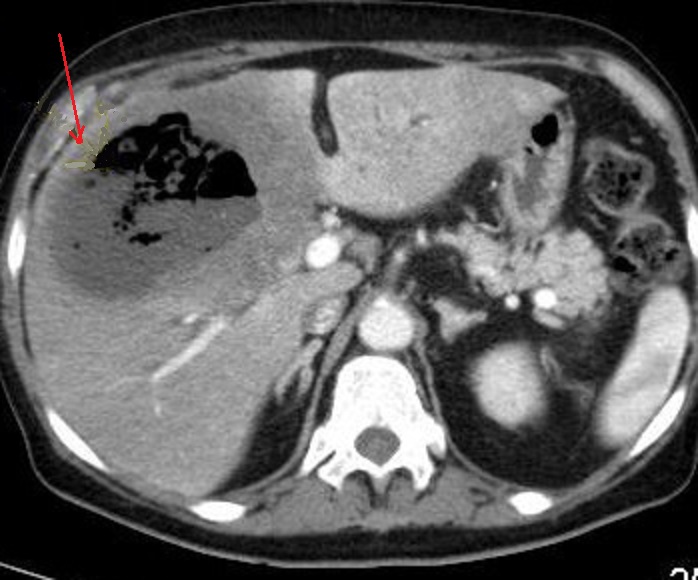

Image radiologique TDM

d'une abces multiple encloisone du foie gauche

( coupe axiale ) |

Image radiologique TDM d'une grande abces amibien du

foie gauche avec aspect lesionnel est une masse

unique, arrondie 10 cm de

diamètre hypodense sur TDM avec

rehaussement de contraste périphérique, contours

réguliers . Image radiologique TDM plus C+ phase

veineuse |

Abces fungique à Candida avait l'aspect TDM semblables aux

abcès à pyogènes :

du foie droit et gauche . Pas image de "cluster

signe " ( grappe de raisin ) est la signe pour

differencie avec abces a pyogenes |